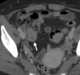

Appendiceal mucocele